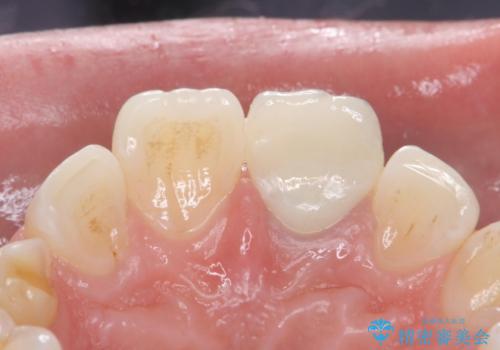

変色した前歯 ジルコニアクラウンでの修復

歯の黒ずみを完全に見えなくすることができ、大変喜んでいただけました。

被せ物を装着する際は、歯の中(根管)から綺麗にすることも重要となります。